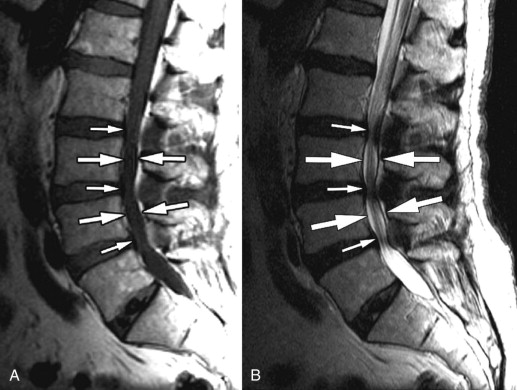

Ob prisotnosti nevroloških znakov ali sumu na utesnitev živčnih struktur je nekoliko primernejša metoda magnetna resonanca, ki strukturne spremembe pokaže nekoliko bolj podrobno, hkrati pa pokaže tudi stanje mehkih tkiv. Z njo lahko ocenimo stanje medvretenčnih ploščic, stanje fasetnih sklepov, zoženje foramnov, prisotnost spinalne stenoze ter morebitne kompresije živčnih struktur.